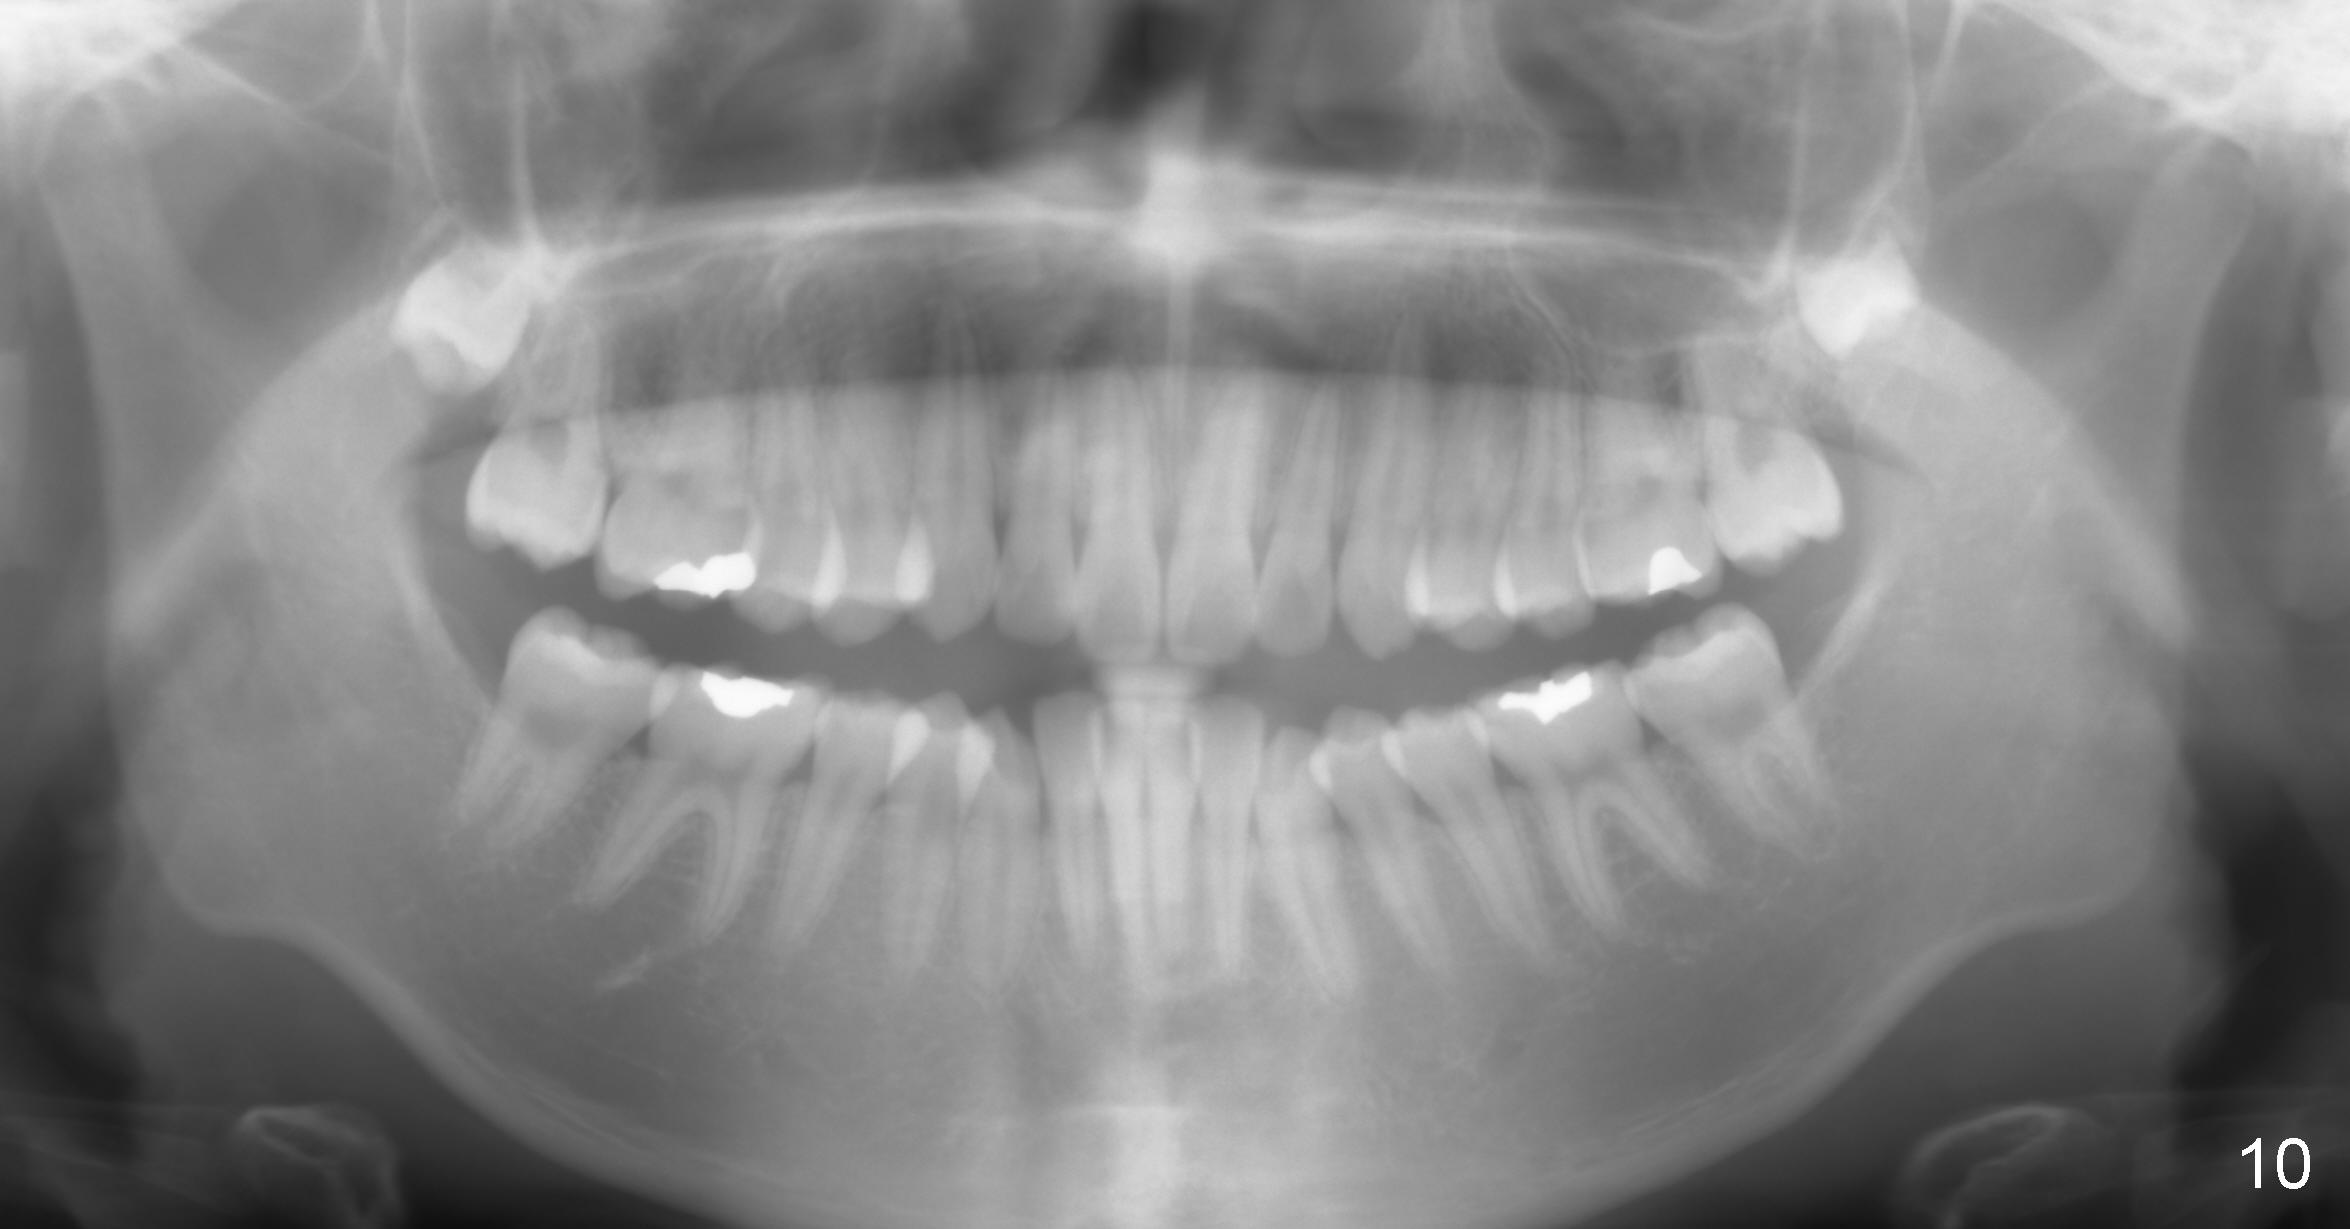

A 15-year-old man wants to improve the facial appearance.

Xin Wei, DDS, PhD, MS 1st edition 02/27/2017, last revision 09/09/2018